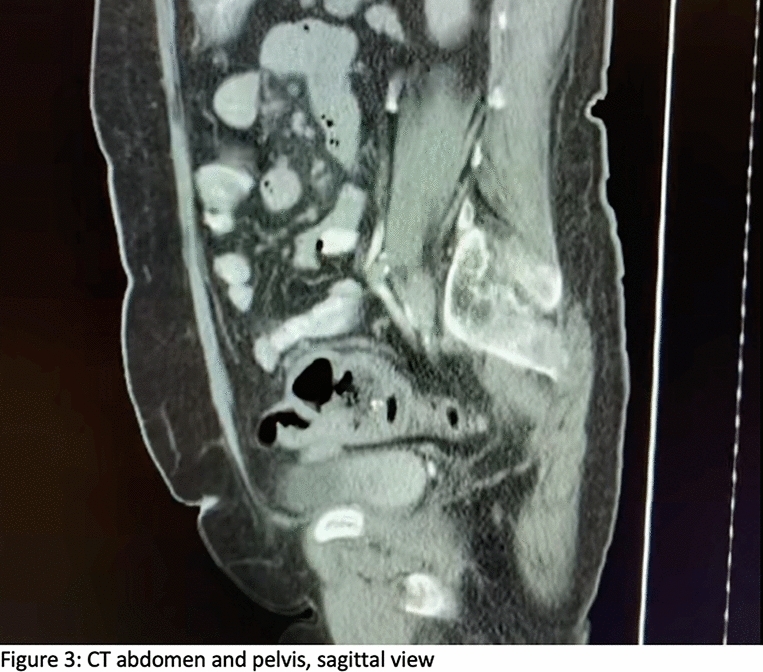

Case Presentation: We report a case of an 81-year-old male who presented to emergency department with incarcerated right inguinal hernia with small bowel contents. During his surgery, he was found to have the urinary bladder adhered to the hernia sac. The hernia sac and the urinary bladder were reduced without any complications. The patient underwent a Lichtenstein tension-free hernia repair.

Conclusion: Inguino scrotal hernia containing bowel contents is not uncommon; however, the presence of the urinary bladder is rare. It should be anticipated intraoperatively, particularly in patients with long-standing hernias. Management is surgical and Lichtenstein repair is a viable option with low rates of recurrence.